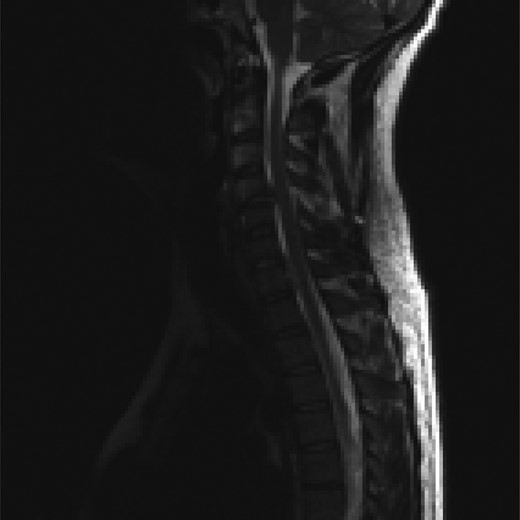

The patient underwent an awake fibre-optic intubation and was placed supine on a Mayfield frame. The subluxation of the C-Spine was reduced with 10 lbs of traction. Neurology noted to be stable after reduction. General anaesthesia induced and a standard left Smyth/Robinson approach taken to anterior cervical spine with level C4–C7 exposed and confirmed on image intensifier. Surgery was performed under full spinal cord monitoring (SCM). The operative team proceeded to perform a discectomy at C4/C5, with a noted tear in the PLL. Fragments from the canal where extracted with the aid of a microscope. Then the team moved to repeat a discectomy at C6/C7, with a small midline tear in the PLL noted. A large fragment was extracted from the canal. Subsequently satisfactory decompression of the cord was achieved and stable somatosensory evoked potentials (SSEPS) and motor evoked potentials (MEPS). Standard fusion was done using a polyethyl ethylketone (PEEK) cage filled with biphasic calcium phosphate (BCP) and a single-level anterior locking plate was employed (Figs 6 and 7).

Sagittal T2-weighted MRI images showing decompression of the cord.